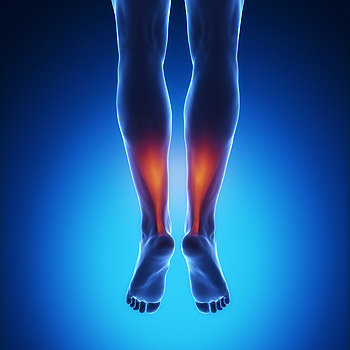

Exercises Can Help Relieve Achilles Tendonitis Pain

Exercises Can Help Relieve Achilles Tendonitis PainMany active people develop what is known as Achilles tendonitis, which occurs when the tendon becomes inflamed over a period of days, rather than suddenly. It is usually the result of repetitive use and the tightening...